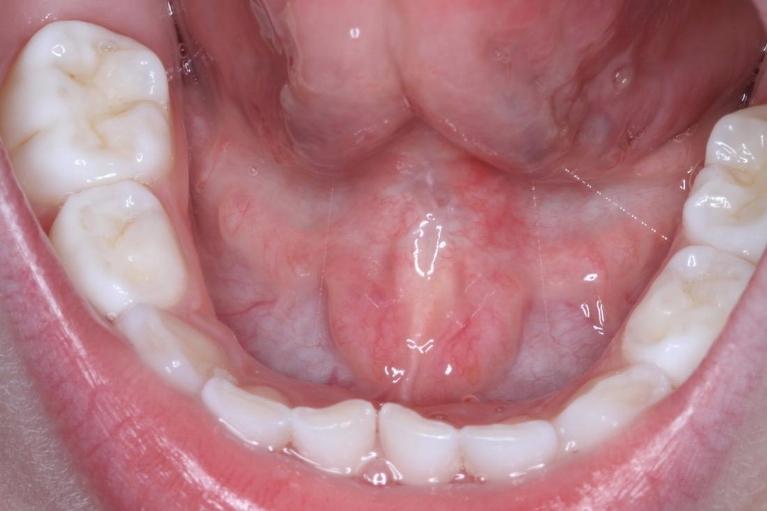

When we hear that a new mom is having difficulty breastfeeding, one of the first things we check is the baby’s frenulum. This is a thin band of tissue that exists between the upper lip and the gum and also between the tongue and bottom of the mouth.

A very tight frenulum, or “tongue tie,” can restrict your baby’s ability to nurse, causing stress for both of you as he or she struggles to latch. Dr. Rick can provide relief for both you and baby with a simple procedure called a frenectomy.

The restricted movement of a tongue-tie makes breastfeeding difficult because your infant’s tongue needs to be in a good position to nurse. If their tongue is restricted and can’t get past the gum, it can’t rest under the nipple to help form a good suction.

A tongue-tie can affect your baby’s ability to nurse successfully, but a severe lip or tongue-tie may even make it difficult for your child to latch onto a pacifier or bottle. Babies with a restrictive frenulum often struggle to receive proper nutrition. A tight frenulum in the mouth can also impact speech development or lead to orthodontic or, digestive issues, and other problems.